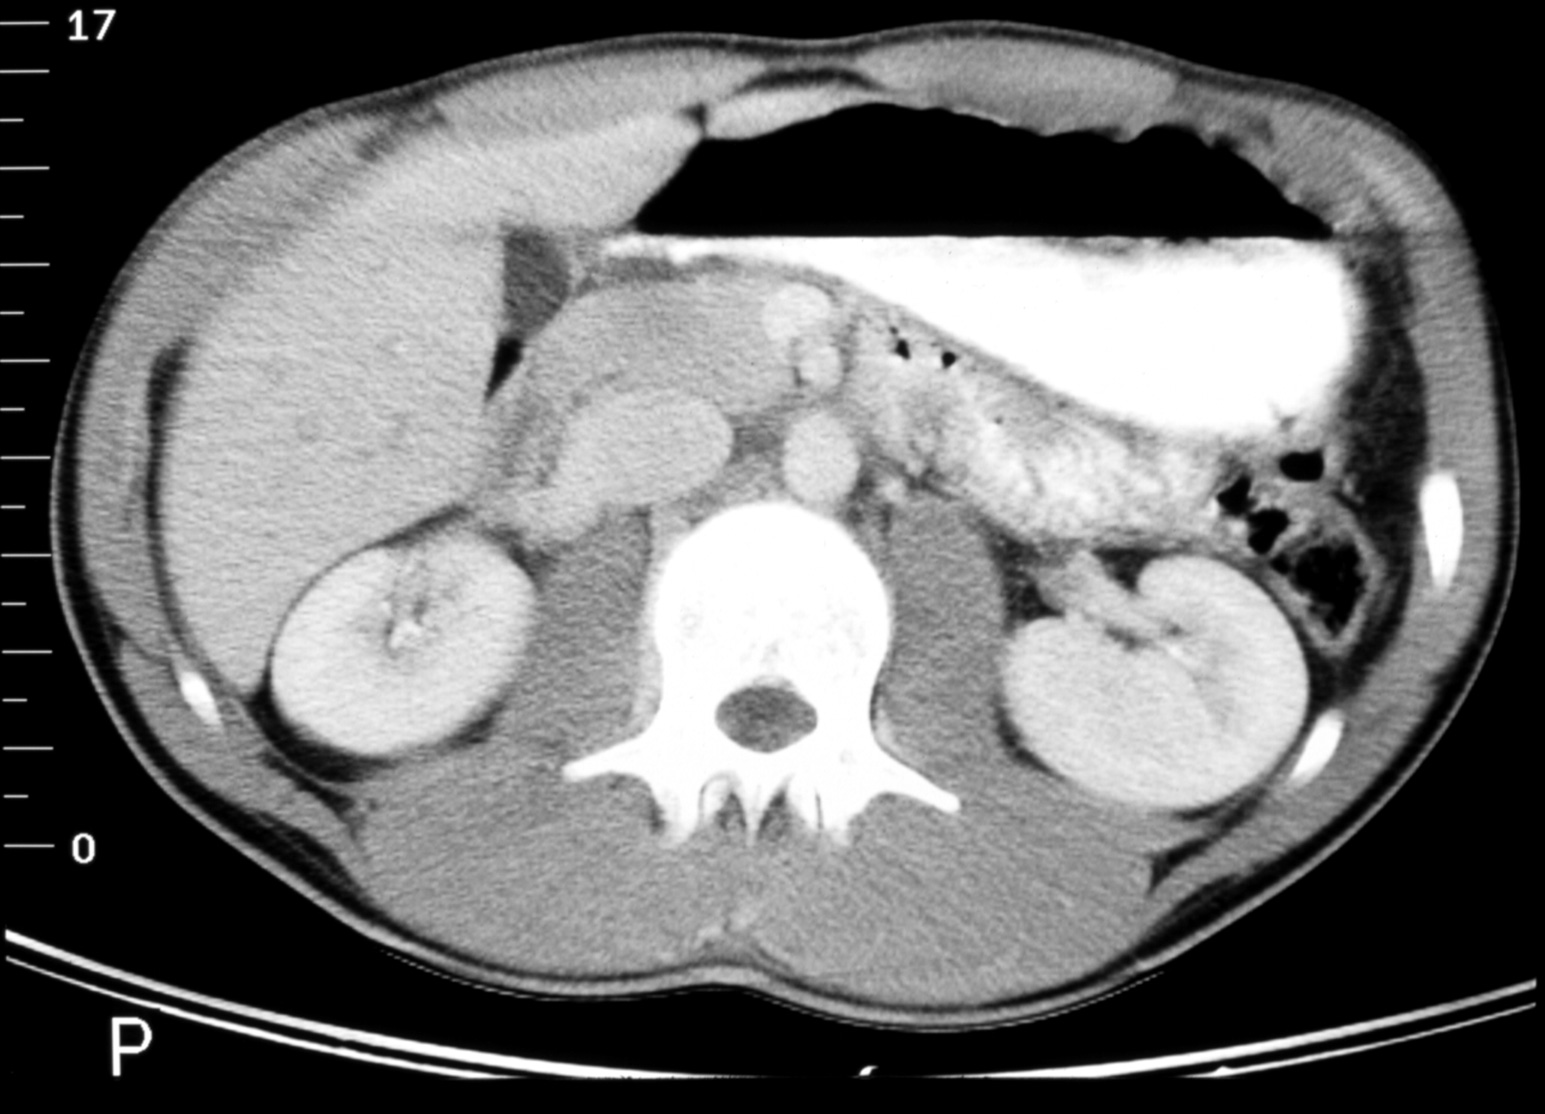

The Structural Basis of Medical Practice

The Pennsylvania State University ©2000

College of Medicine